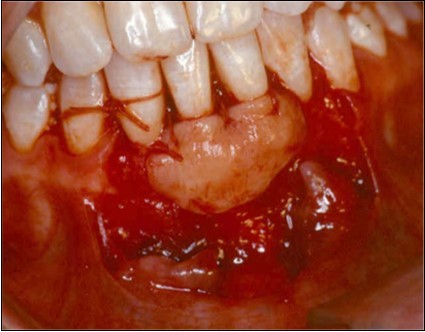

Donor Site

A second surgical site is created on the palate. The length of this is determined by the combines width of the teeth to be covered. The incisions are made in an anterior posterior direction. They are carried to the depth of the palatal mucosa, where they converge just short of the bone. A wedge of tissue is removed as free gingival graft, and its band of epithelium is excised by using Er:YAG laser and acute dissection with scalpel and blade 15C (Figure 4, Figure 4A). The graft is placed in the previously recipient site so that it completely covers the formerly exposed root area (Figure 5). It is then firmly sutured in place with 5-0 gut. The partial thickness, flap is positioned coronally in a manner to cover as much of the graft as possible and sutured in this position to promote maximum adaptation to ensure better healing with less chance of wound dehiscence (Figure 6). The donor site and recipient site is covered with surgical dressing and the patient is instructed in normal postsurgical management. The patient is seen on the 7th postoperative day to remove the surgical dressing and sutures. No additional dressing is necessary, and normal plaque control techniques are resumed (Figure 7)

Figure 4.Donor site area in the palate

Figure 4a.Elimination of the epithelium from free gingival graft by acute dissection